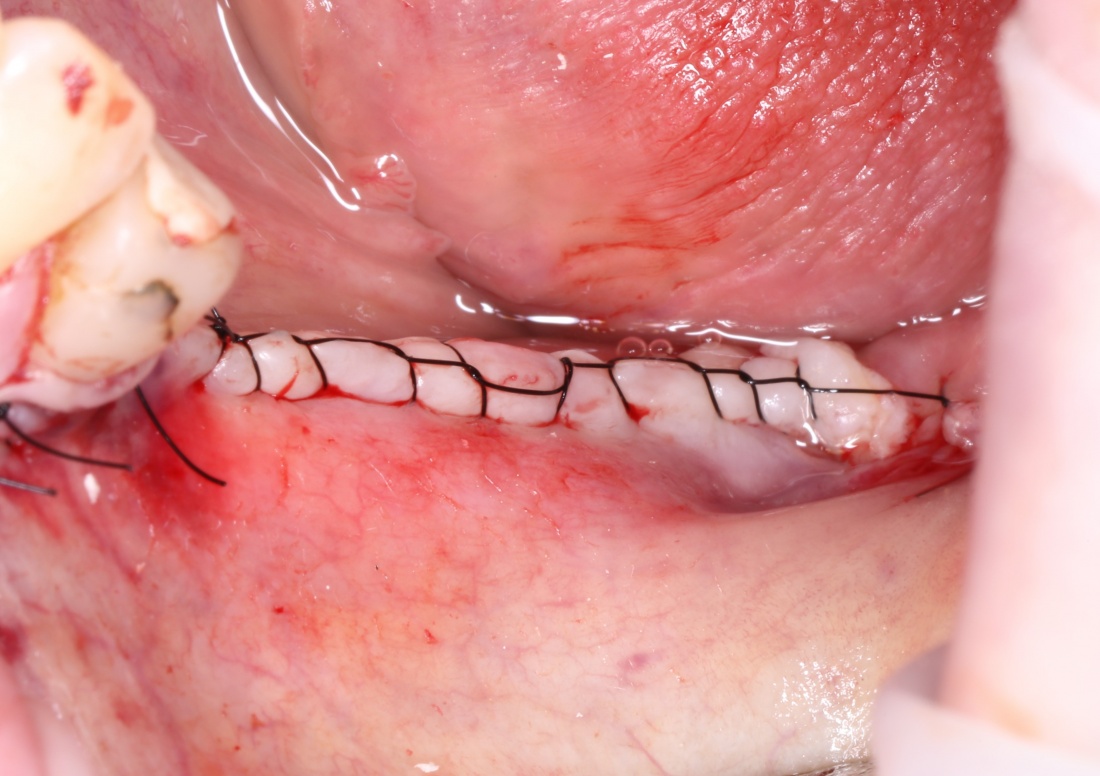

Осталось только наложить швы:

и подождать 3-4 месяца до интеграции имплантов.